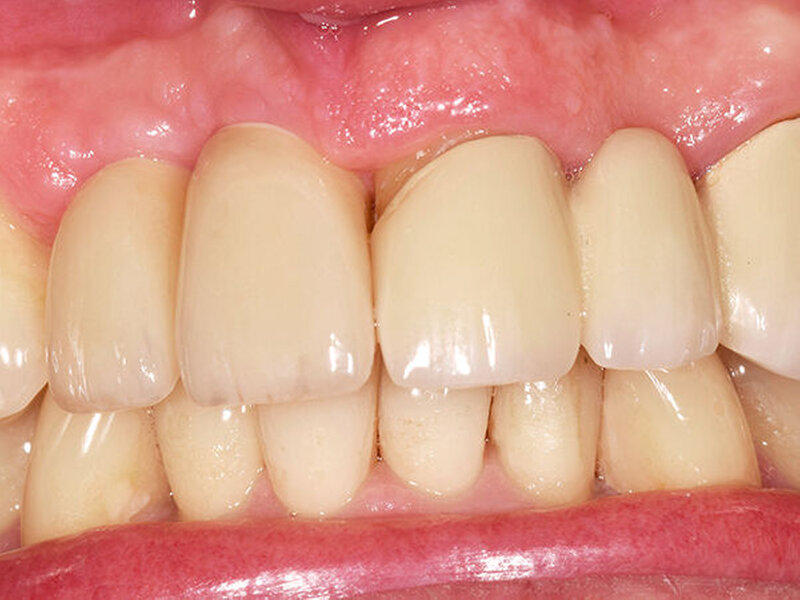

Drei Monate nach Einsetzen der definitiven Kronen erschien der Patient zur finalen Kontrolle in unserer Sprechstunde. Die keramischen Kronen (Cercon Ceram Kiss, Degudent) sind auf individuellen CAD/CAM-gefertigten Abutments (DEDICAM, CAMLOG) zementiert (Ketac Cem). Die Röntgenaufnahme zeigte osseointegrierte Implantate mit gesunder Knochenstruktur und im periimplantären Bereich keine überschüssigen Zement‧reste (Abb. 12). Die Kronen fügen sich in Form und Farbe natürlich in die Zahnreihe ein (Abb. 13). Das Emergenzprofil zwischen 13 und 12 ist aus unserer Sicht suboptimal, jedoch bei tiefer Lachlinie für den Patienten nicht relevant. Dieser ist mit seiner metallfreien Versorgung sehr zufrieden.